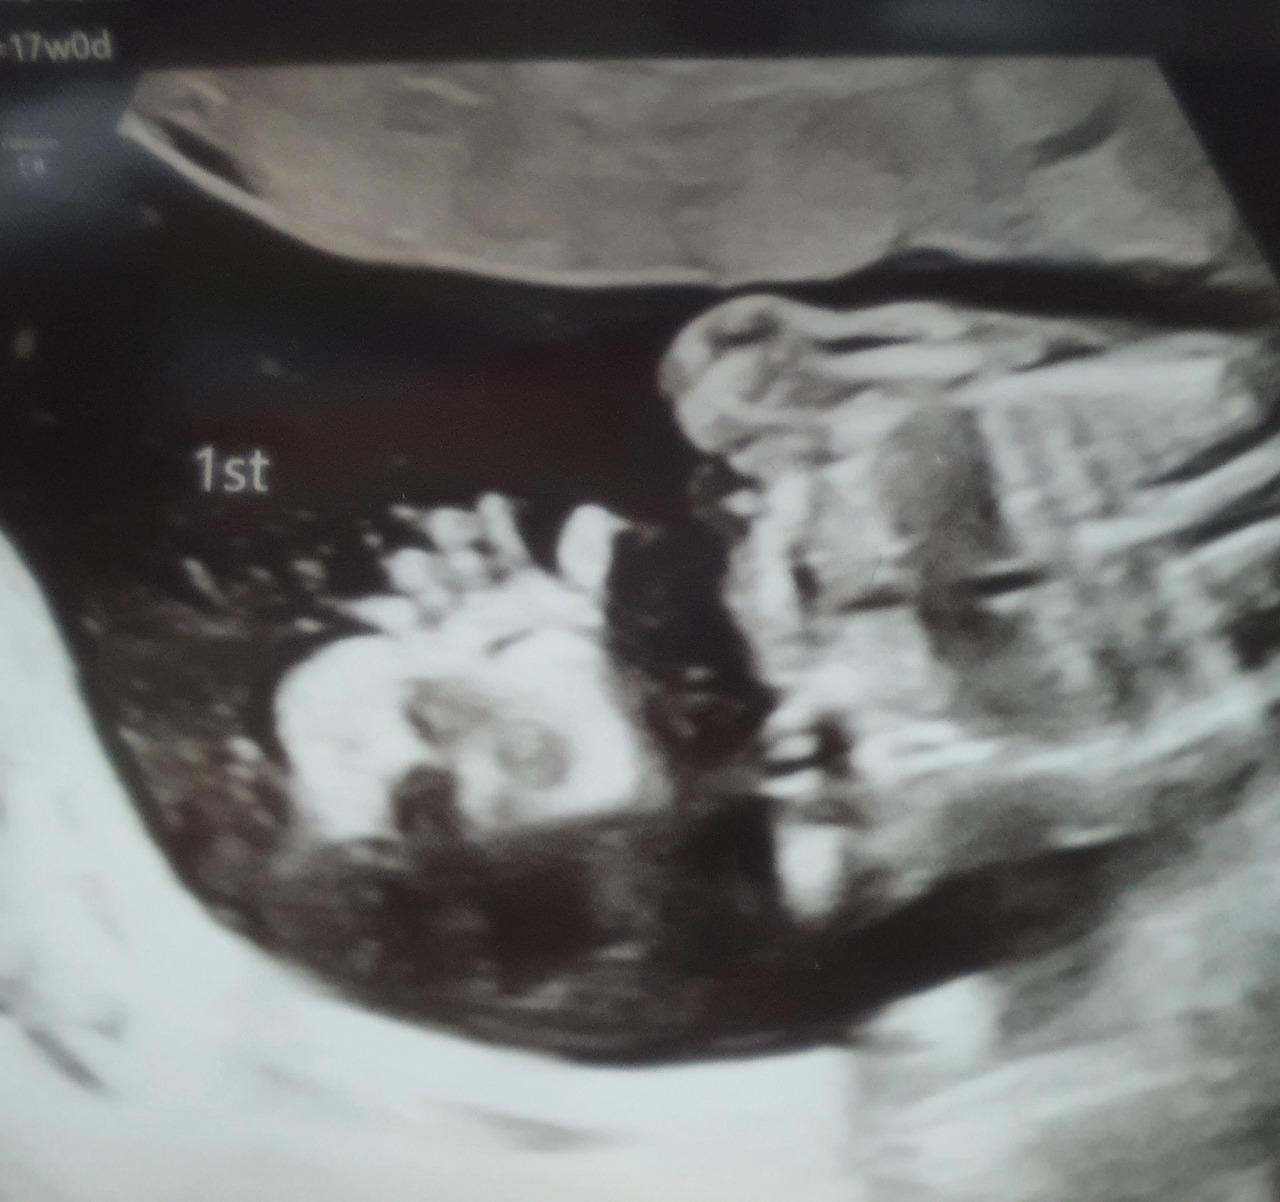

Hi! 17주 0일. 나에게 인사해주는 고명딸